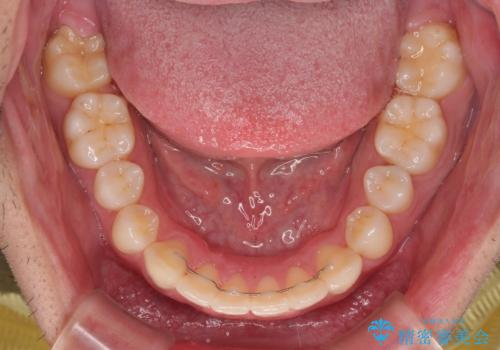

インビザラインによる矯正治療をご希望でしたが、上顎歯列の前方位と鋏状咬合を確実に改善することを目的として、補助装置を併用することとしました。

補助装置を併用せずに治療を終える可能性はありましたが、確実に結果を得るために補助装置を活用しました。

イメージしたとおりの仕上がりとなりました。